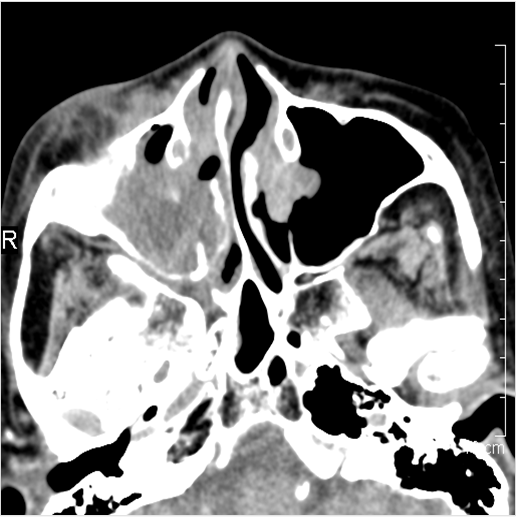

The fat planes in the canine fossa deep to the SMAS are infiltrated. [Yes/No]

The extraconal orbital fat surrounding the infraorbital vascular bundle is infiltrated. [Yes/No]

The fat pad posterior to the maxillary sinus and within the pterygopalatine fossa are infiltrated. [Yes/No]